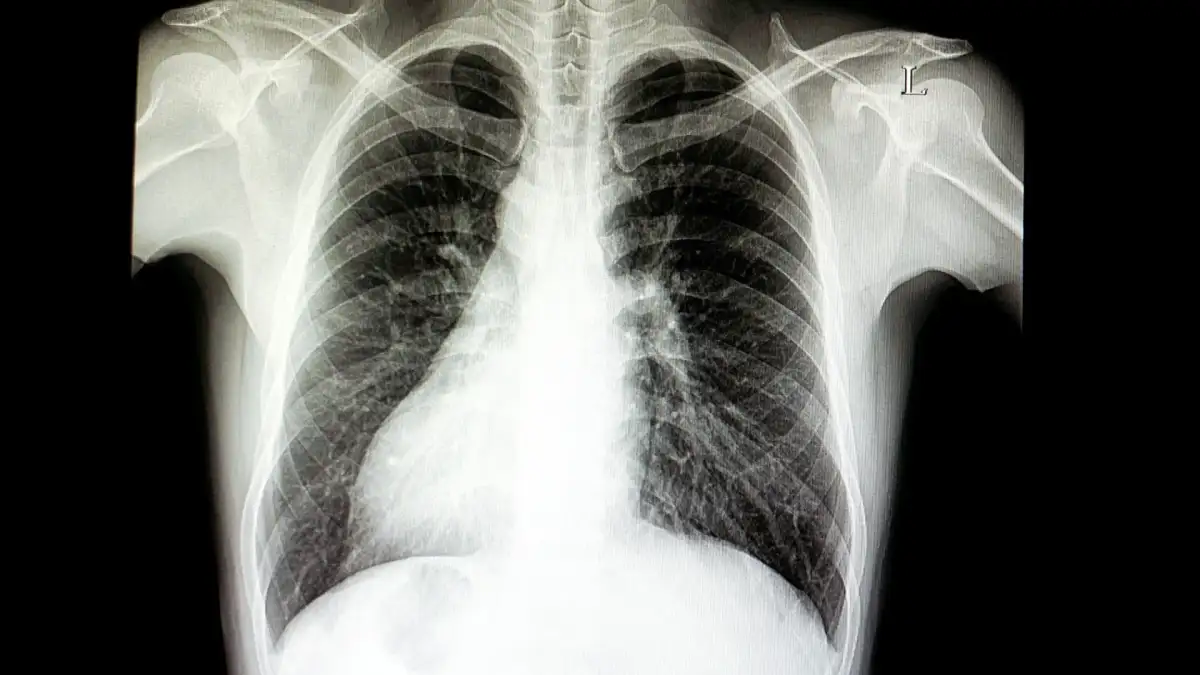

In a reality where biology occasionally veers off its presumed course, Randy Foye, a former NBA point guard, lives with situs inversus. This condition, a rare congenital anomaly, dictates that his major visceral organs are positioned in a mirrored fashion to the typical human anatomy. His heart, rather than residing on the left, is situated on the right side of his chest, with his liver also taking up a leftward position.

Situs inversus affects approximately 1 in every 10,000 births. It represents a significant deviation from the standard organ arrangement, known as situs solitus. The precise causative factor for this genetic mutation remains an enigma, with scientists acknowledging its presence without fully comprehending its origin. While some cases of situs inversus might coincide with other health issues, such as congenital heart disease or primary ciliary dyskinesia, many individuals experience no related complications.